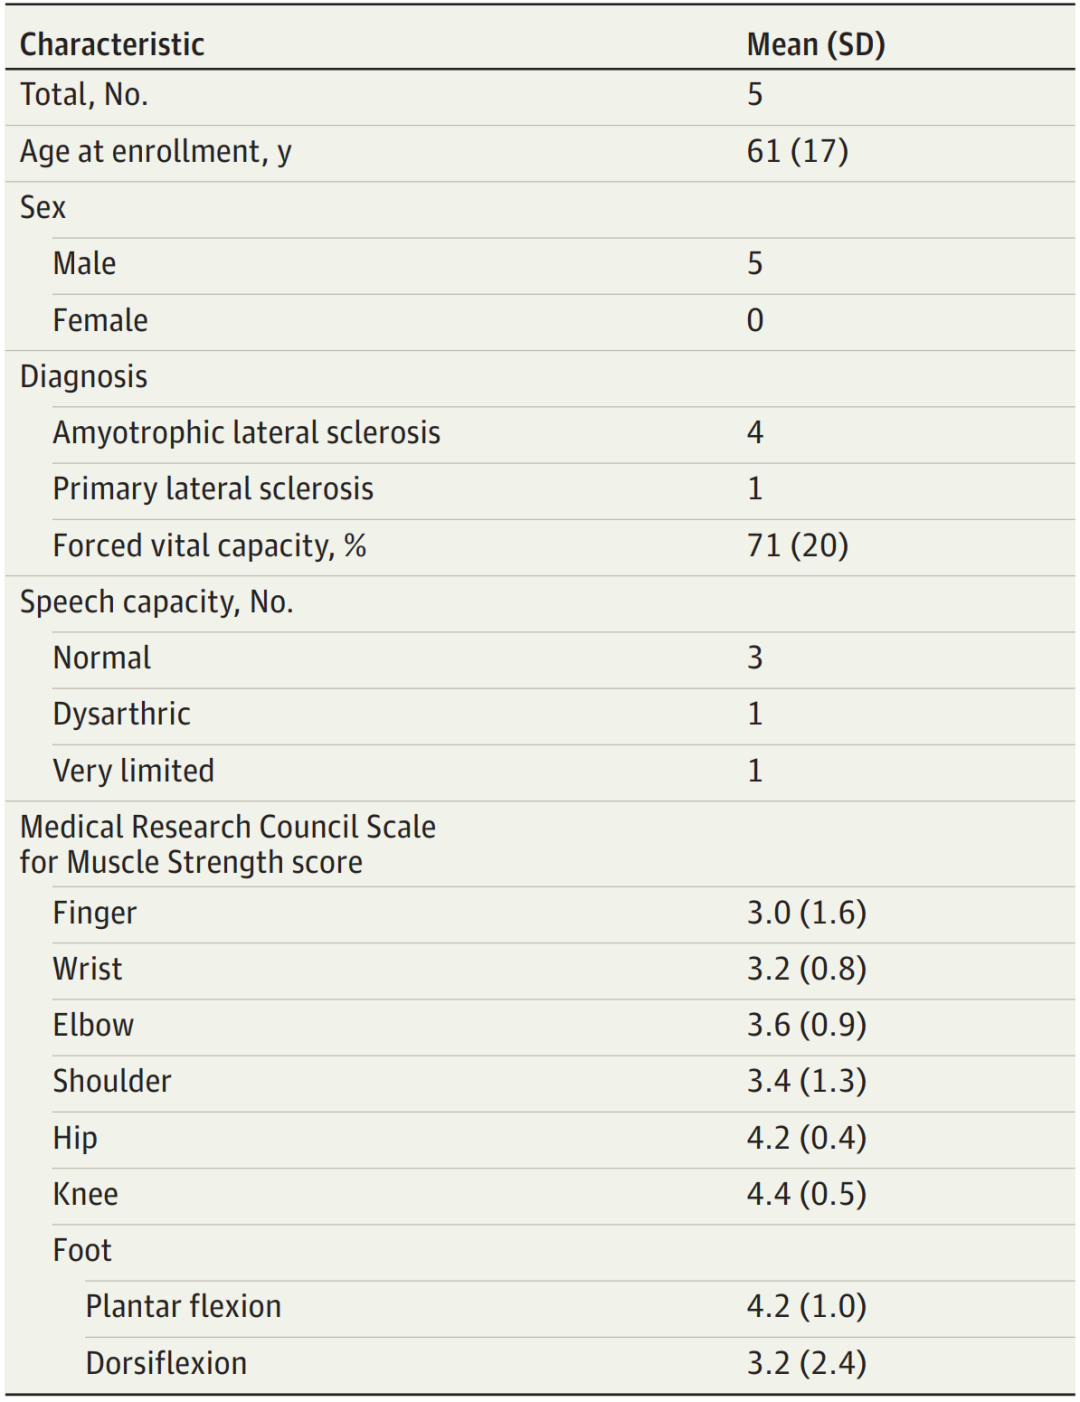

为期12个月,5名患者参加了这项研究(表1)。所有患者均为男性,欧洲血统,患有严重上肢瘫痪,4例患有肌萎缩性侧索硬化症(ALS), 1例患有原发性侧索硬化症。患者在入组时肺功能和语言能力有不同程度的损伤。记录设备被植入靠近中央前回的上矢状窦中,并与植入同侧锁骨下皮的电子设备相连。整个过程取平均值232分钟,包括植入后设备的术中测试。

表1.研究参与者基线特征